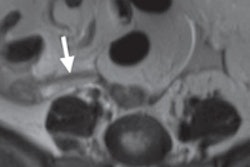

The researchers then determined the diagnostic performance of studies that were designated as 5a and 5b. They also used multivariate analysis to correlate eight specific ultrasound findings with perforation: maximum appendiceal diameter, wall thickness, loss of mural stratification, hyperemia, periappendiceal fat inflammation, periappendiceal fluid, lumen contents, and appendicolith presence. For the purposes of the study, surgical diagnosis and clinical follow-up served as the reference standards.

However, the researchers did discover that six findings had a statistically significant association with perforation.

| Complex periappendiceal fluid | 18.5 | < 0.001 |

"A longer duration of symptoms and several [ultrasound] findings are significantly associated with perforation, especially the presence of complex periappendiceal fluid, as well as greater maximum appendiceal diameter and the presence of an appendicolith," the authors concluded. "Particular attention should be paid to these imaging findings when interpreting [ultrasound] studies for pediatric appendicitis, especially when nonsurgical treatment is being considered."